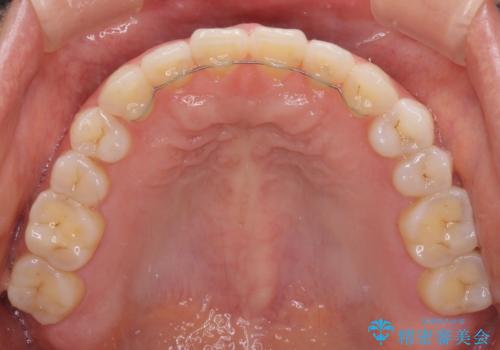

- 上下の前歯の隙間を気にして来院された患者様です。

インビザラインを用い、上下歯列のスペースを閉じていくこととしました。

治療期間中は奥歯がほとんど咬めない状態が続き、食事に大変苦労されました。

最終的には隙間もしっかりと閉じ、奥歯も咬みやすい状態でしあげることができました。